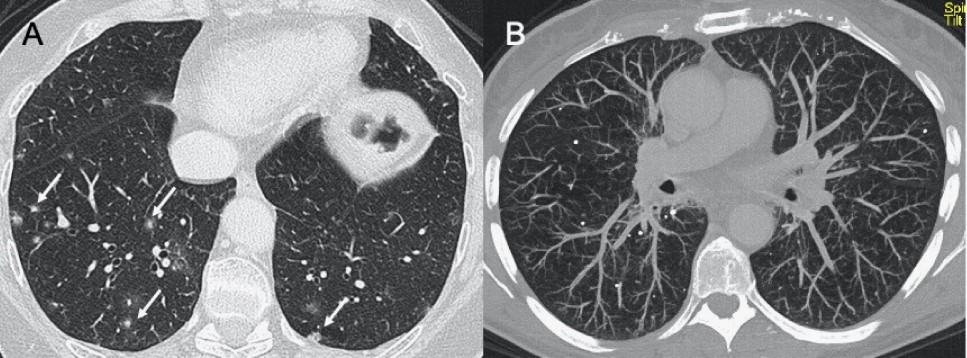

● CXR:雙側(cè)網(wǎng)狀結(jié)節(jié)狀影伴實(shí)變區(qū),通常在下葉。

● CT:GGO多灶性實(shí)變和彌漫性區(qū)域,還可能觀察到淋巴結(jié)病變、空洞形成、胸腔積液。

圖3 圖(A-C)顯示了一例與COVID-19間質(zhì)改變相似的甲型流感病例:GGO主要分布在胸膜下和雙側(cè),呈小葉周圍性分布。圖(D)為同一患者的仰臥位胸片,可見(jiàn)彌漫性間質(zhì)受累。

?HINI流感病毒

● CXR:?jiǎn)蝹?cè)/雙側(cè)GGO,伴或不伴實(shí)變區(qū)域,主要分布于支氣管血管周圍和胸膜下。

● CT:?jiǎn)蝹?cè)/雙側(cè)GGO,伴或不伴實(shí)變區(qū)域,主要分布于支氣管血管周圍和胸膜下。

圖4 圖(A-D)為一例H1N1相關(guān)肺炎并發(fā)急性呼吸窘迫綜合征(respiratory distress syndrome,ARDS)的影像,可見(jiàn)彌漫性和雙側(cè)GGO以及牽引性支氣管擴(kuò)張。